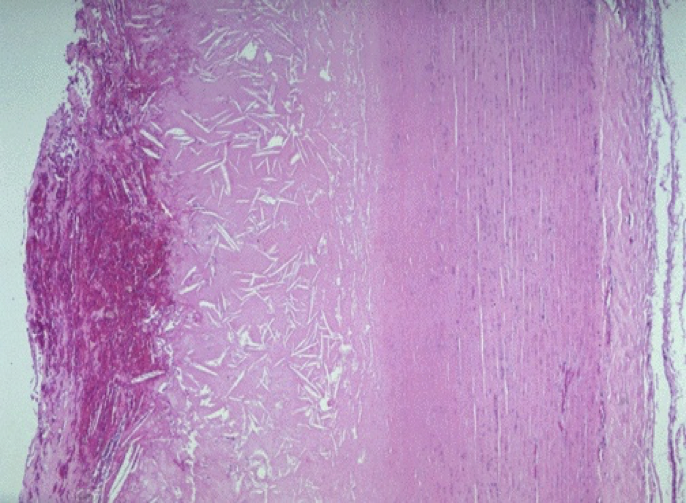

3.粥样斑块(atheromatous plaque) 亦称粥瘤(atheroma)。

(图3-6)

肉眼观:动脉内膜面见明显隆起的灰黄色斑块。切面见纤维帽的下方有黄色粥糜样物。

光镜下:在玻璃样变的纤维帽的深部为大量无定形坏死物质,其中可见胆固醇结晶(HE片中为针形或梭形空隙,图3-9)及钙化。坏死物底部及周边可见肉芽组织、少量FC和淋巴细胞。病灶处中膜平滑肌受压萎缩而变薄。外膜可见毛细血管新生、结缔组织增生及淋巴细胞、浆细胞浸润(图3-8)。

(图3-8)

(图3-9)